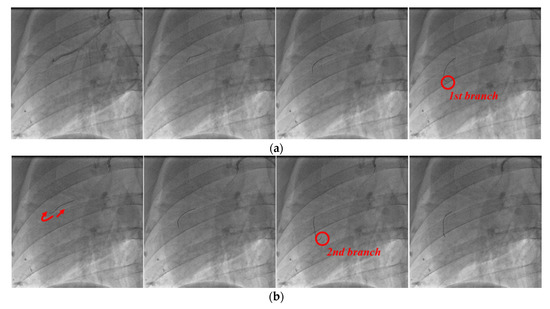

The angiography images of each stage in the process of guidewire advancement are shown in Figure 16. The guidewire was advanced, and it reached the first branch point, as shown in Figure 16a. Then, the guidewire was withdrawn from the first branch by moving it backward and rotating it, and it was advanced again to reach the second branch, as shown in Figure 16b. Finally, the guidewire was retracted and rotated again to exit from the second branch point, and then it was advanced to successfully reach the final target location, as shown in Figure 16c. In postoperative observation, the physician confirmed that there were no complications, such as perforation or bleeding.

Figure 16. Angiographic views of the right coronary artery of the pig. Process of inserting guidewire into (a) first branch, (b) second branch, and (c) final target.